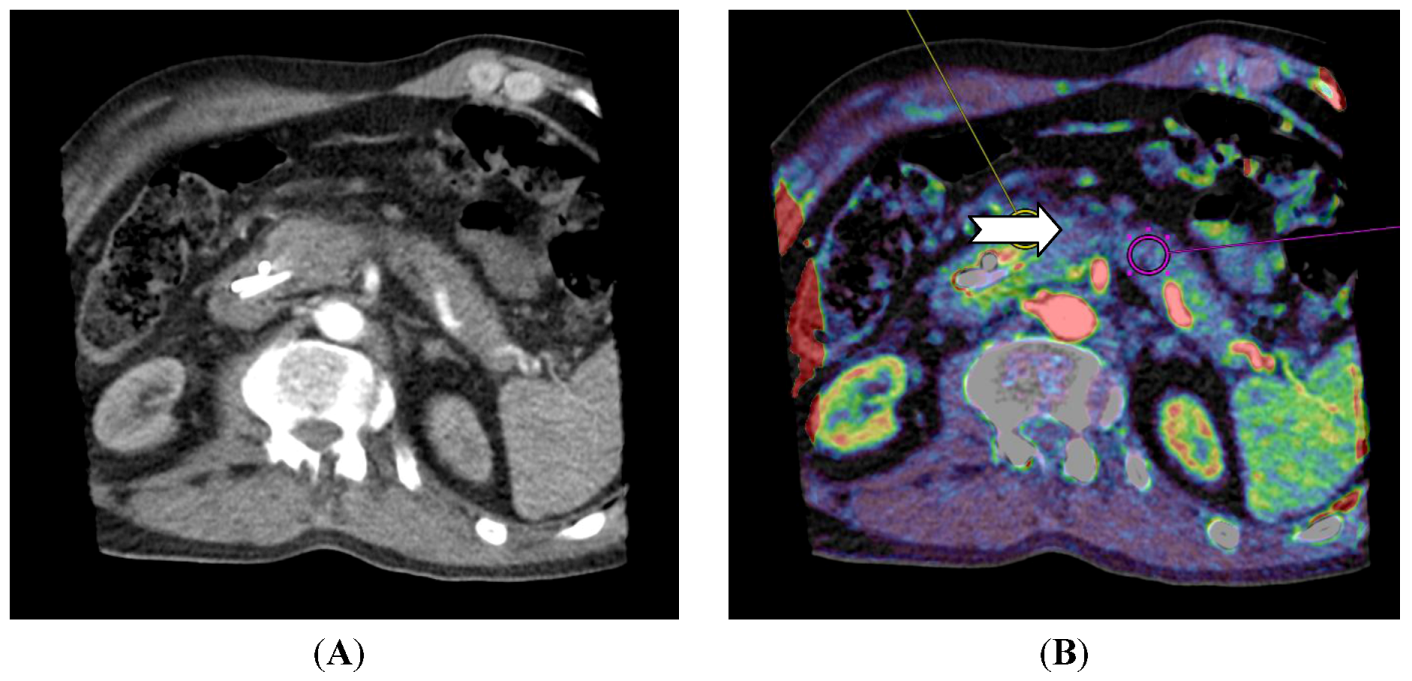

Figure 4.

CT perfusion examination of a 63-year-old male with a pancreatic mass. The tumor has a neuroendocrine component and CT perfusion shows higher blood flow (110.2 mL/min/100 mL) (arrow) compared to the normal pancreatic tissue (83.7 mL/min/100 mL) (B). The patient has stents in the common bile duct (A) which causes image and perfusion artifacts in the pancreatic head. (Images reconstructed with Vitrea 6.2, Vital Images A Toshiba Medical Systems Group).